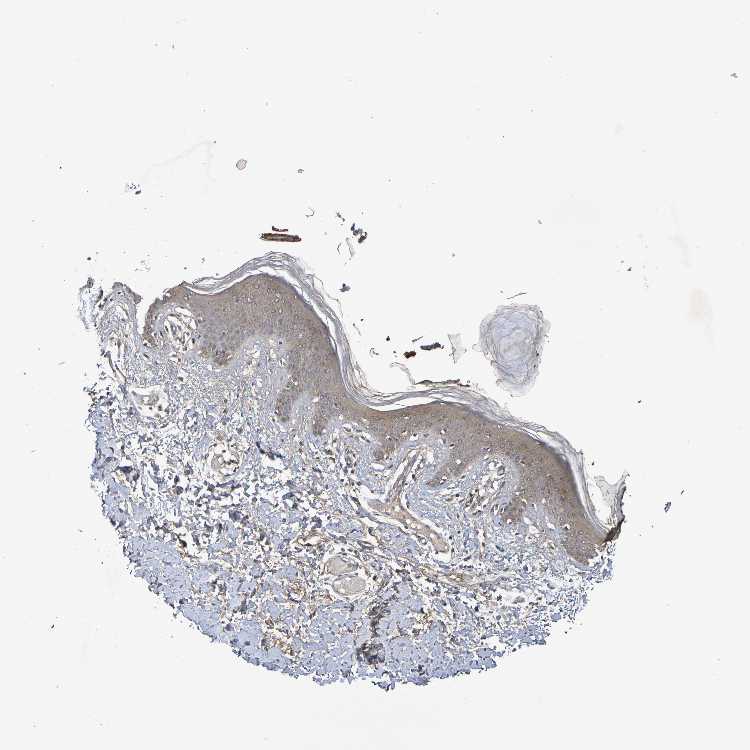

SKIN 2 - Antibody stainingi

Antibody staining in the annotated cell types in the current human tissue is reported as not detected, low, medium, or high, based on conventional immunohistochemistry profiling in selected tissues. This score is based on the combination of the staining intensity and fraction of stained cells.

Each image is clickable and will lead to virtual microscopy that enables deeper exploration of all samples and also displays staining intensity scores, fraction scores and subcellular localization as well as patient and tissue information for each sample.

Antibody HPA001907Antibody HPA002735Antibody CAB010451Antibody CAB080271

Epidermal cells MediumHighMediumHigh